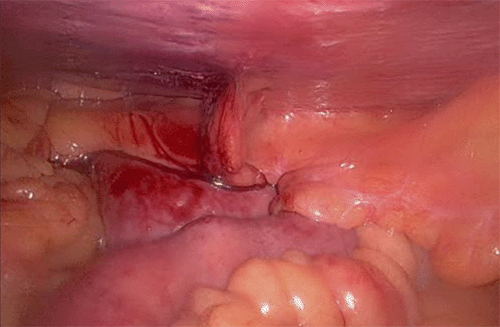

Figure 2. Intraoperative View of Bilateral Morgagni Hernias and Contents. Published with Permission

Intraoperative photographs depicting the anterior diaphragm with bilateral Morgagni hernia defects. The larger right-sided defect is shown containing herniated loops of small bowel, while the left-sided defect contained omentum prior to reduction

Due to the difficulty in mobilizing the large bowel and lysing extensive adhesions, a combined right video-assisted thoracic surgery (VATS) and robotic-assisted laparoscopic approach was utilized to achieve complete reduction of the herniated viscera and excision of the hernia sac. Once the abdominal contents were fully reduced into the peritoneal cavity, attention was turned to the diaphragmatic defects using the robotic platform. A profound loss of domain became immediately apparent upon reduction of the viscera (Figure 3). Insufflation, even at increased pressures, provided inadequate visualization and minimal working space for robotic instrumentation, confirming acute LOD. Each defect was then repaired individually using a 2 mm thick Gore-Tex mesh, tailored and secured as an inlay graft with initial 0-silk horizontal mattress corner sutures followed by a running 0-V-Lock nonabsorbable suture circumferentially (Figure 4). The mesh was anchored to the anterior abdominal wall. The smaller left-sided defect was primarily closed with interrupted 0-silk horizontal sutures. The assistant port site was closed using a Carter-Thomason suture passer with #1 Vicryl, while robotic port sites were closed with 2-0 Vicryl subdermal sutures followed by 4-0 Monocryl subcuticular sutures.